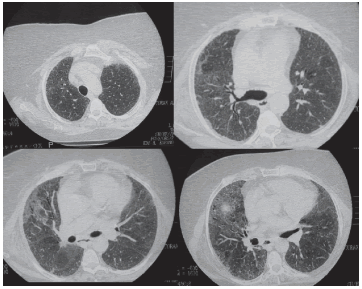

En ese momento presentaba una tomografía axial computada de alta resolución (TACAR) de tórax que se muestra en la Figura 1 y otra de un año atrás (2009) en la Figura 2.

Dr. Rossi: En la TACAR se observa alteración del

intersticio pulmonar dado por engrosamiento de

los septos subpleurales e interlobares, bilaterales,

con opacidades en vidrio esmerilado subyacentes.

Con mayor compromiso del lóbulo medio y ambos

lóbulos inferiores, se observa presencia de bronquiectasias y bronquioloectasias por tracción, sin

evidencia de panalización franca. Si bien el estudio previo difiere en calidad y técnica, no parecen

existir cambios significativos en el transcurso del

año previo a la consulta.

Se observan además un elastofibroma dorsal bilateral, ganglios calcificados secuelares en espacio

paratraqueal inferior derecho e hiliar homolateral.

Prominencia del tronco de la arteria pulmonar y

hernia hiatal por deslizamiento.

Desde el punto de vista de las imágenes deberíamos considerar neumonía intersticial no específica

(NINE) del subtipo fibrótica, aunque si tenemos

en cuenta la clasificación del último consenso sobre fibrosis pulmonar idiopática (FPI) del 20111;

podríamos encasillarlo dentro de posible NIU.